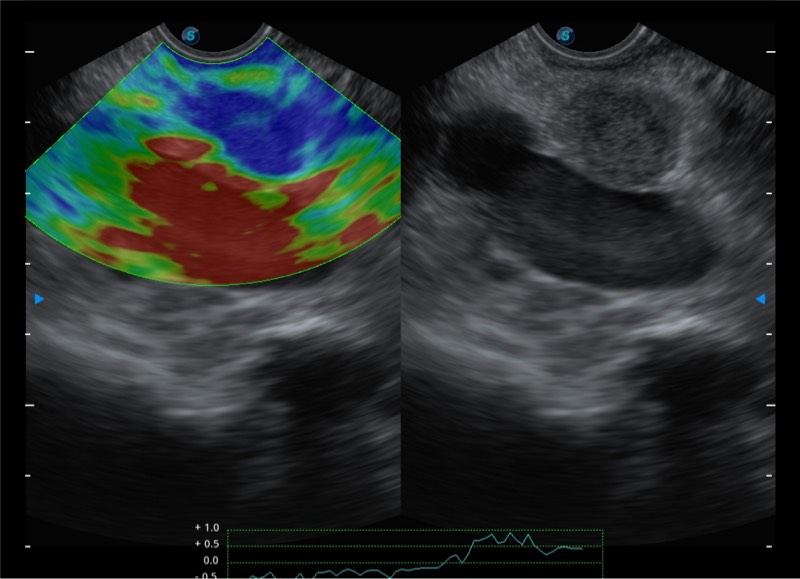

搭载百万级CMOS成像技术

及自主研发凸阵换能器,

可呈现优质的内镜和超声画面

基于二十年的超声技术积累,球速体育入口提供了最新一代的独立超声主机,在提供高质量图像的同时满足多学科使用。具备常见多普勒技术并提供弹性成像、声学造影等高端影像技术。新一代传感器具有更强的抗干扰能力并减少图像伪影。

4-12MHZ宽频输出